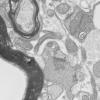

Neuroaxonal dystrophy (3)